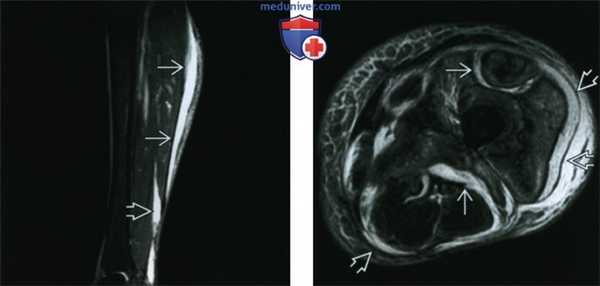

(Слева) Сагиттальная STIR МР-И: высокий сигнал от жидкости, располагающейся между медиальной головкой икроножной мышцы и подкожной жировой клетчаткой. Также визуализируются глубокие фасциальные скопления жидкости между глубоким сгибателем и ахилловым сухожилием. Признаки характерны, но неспецифичны для некротизирующего фасциита.

(Справа) Аксиальная Т2 ВИ FS МР-И: распространение жидкости по глубоким и поверхностным фасциям и их утолщение, наряду с отеком подкожной жировой клетчатки и мышц. В этом тяжелом случае некротизирующего фасциита потребовалась ампутация.